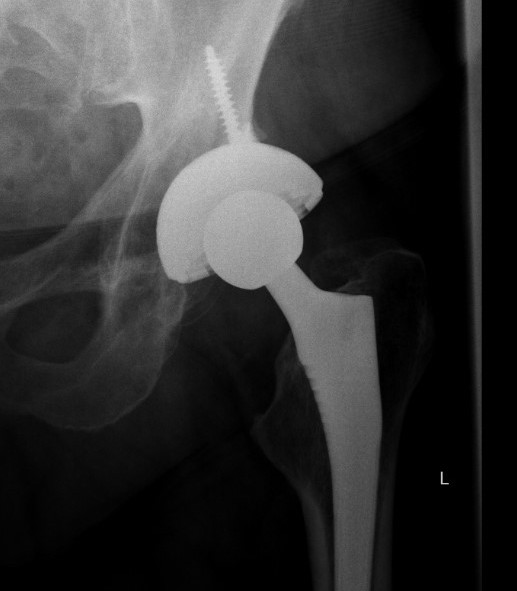

Complications

Acetabular fracture

Increased risk

- small acetabulum

- under-reaming

- elderly / osteoporotic bone

Management

- screws

- posterior column plating

- cage

Failure of initial acetabular press fit

Acetabular spin out